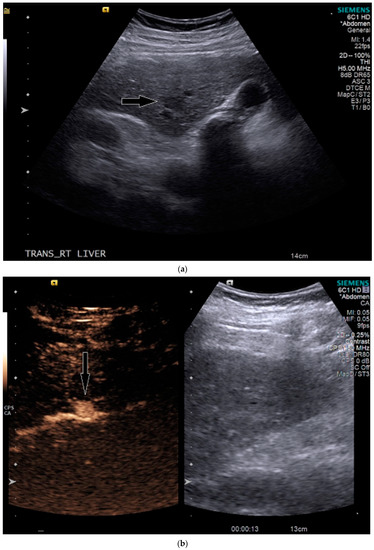

On grayscale US, a subtle 1.2 cm hypoechoic focal area was identified on a background of echogenic, heterogeneous liver echotexture (Figure 3). This area was targeted with contrast, which showed avid arterial-phase enhancement, and rapid, but mild washout (Figure 3). This was also designated LI-RADS M due to the early washout. CT was performed to confirm the finding and initially, the lesion was not identified by the radiologist, despite a diagnostic late arterial phase. On closer inspection with the US finding in mind, subtle enhancement and washout on the CT was seen and considered LI-RADS 4 (Figure 4), and due to this designation and its small size, a shorter interval follow-up was performed at 3 months rather than 6 months.

Figure 3.

Patient 2 ultrasound images, with liver lesion denoted by black arrow: (a) grayscale images showing the hypoechoic lesion. Post contrast administration ultrasound in arterial phase (b) and early washout (c) of the lesion, LI-RADS M.